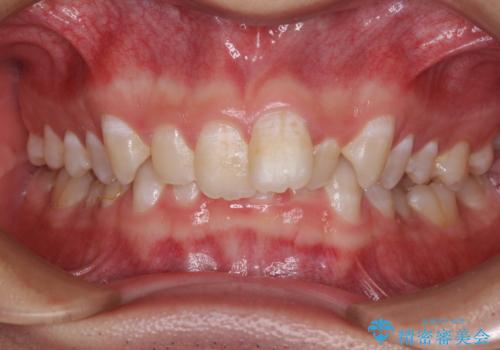

- 強い咬み合わせと前歯のデコボコを気にして来院された患者様です。

下顎前歯が全て隠れてしまうほどの深い咬合で、左右の奥歯は1歯対1歯で咬み合う状態でした。